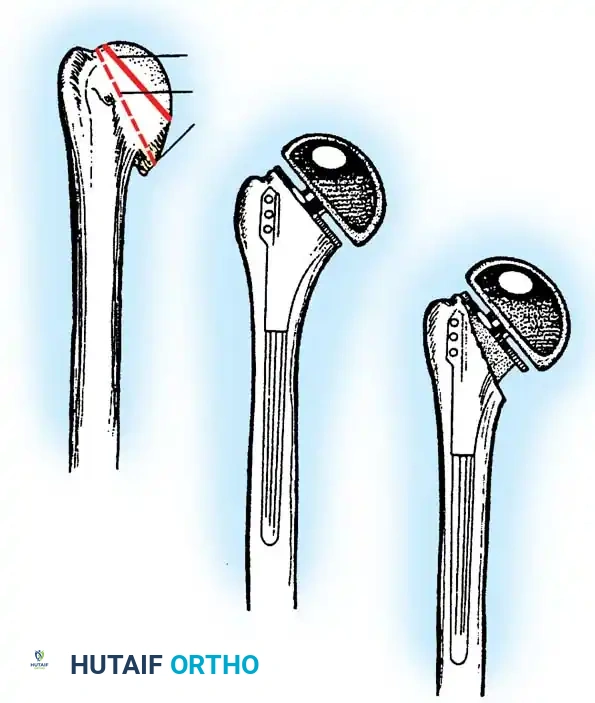

3. Humeral Head Resection

Dislocate the humeral head anteriorly through external rotation and extension. Remove peripheral osteophytes to identify the true anatomical neck. The humeral cut is made along the anatomical neck, typically at 30 degrees of retroversion and 45 degrees of inclination.

Reverse Total Shoulder Arthroplasty (rTSA)

The rTSA fundamentally alters shoulder biomechanics. By medializing and distalizing the center of rotation, it increases the deltoid moment arm and recruits more anterior and posterior deltoid fibers for elevation, bypassing the need for a functional rotator cuff.

Surgical Nuances for rTSA:

* Glenoid Baseplate: Must be positioned inferiorly on the glenoid to avoid scapular notching. A slight inferior tilt (10 degrees) is often utilized.

* Glenosphere: Typically 36 mm or 42 mm. Larger spheres increase stability and range of motion but may increase the risk of notching.

* Humeral Stem: Often placed in 0 to 20 degrees of retroversion.